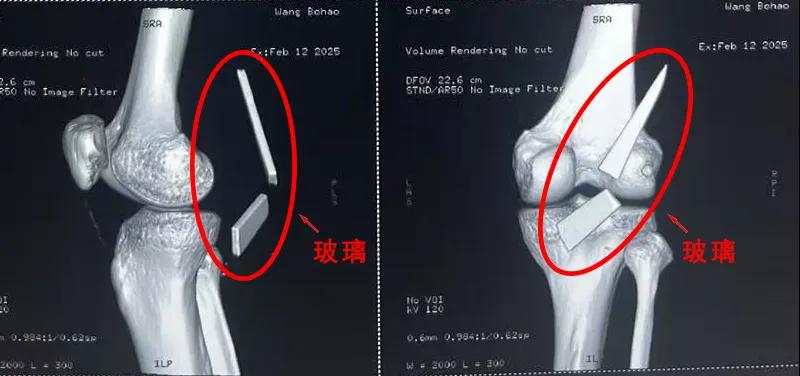

13厘米碎玻璃扎入腿中,漯河醫(yī)專二附院顯微外科緊急“拆彈”......

患者家屬這才開始意識到問題的嚴重性,便帶著孩子到鄉(xiāng)鎮(zhèn)衛(wèi)生院檢查——結(jié)果顯示右膝關(guān)節(jié)后方竟然殘留著兩塊兒鋒利的碎玻璃,測量后預估玻璃總長將近13厘米!

由于玻璃位置毗鄰坐骨神經(jīng)和股動脈,一旦刺破股動脈,將嚴重威脅生命。家屬著急萬分,想著能否盡快手術(shù)取出碎片,于是慕名來到漯河醫(yī)專二附院(漯河市骨科醫(yī)院、漯河市立醫(yī)院)手顯微外科(修復重建骨感染科)。

術(shù)中,馬廣輝醫(yī)生憑借扎實的理論知識和嫻熟的顯微外科技術(shù),順利找到深深刺進肌肉的兩塊玻璃,肉眼可見玻璃尖端距股動脈僅有不到半公分的距離!如果患者再耽誤半天或者再多活動幾次膝關(guān)節(jié),小指粗的股動脈很有可能被玻璃扎破,后果難以想象。

最終,馬廣輝醫(yī)生在血管、神經(jīng)表面順利取出兩塊玻璃碎片,拆除了埋在患者膝關(guān)節(jié)的“炸彈”。在告知患者家屬術(shù)中情況后,家屬懸著的心終于放了下來。